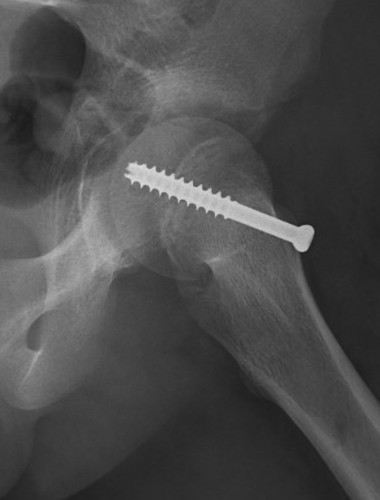

Intra-capsular / Subcapital

Types

Dunn

- trapezoid osteotomy

Fish

- cuneiform

Advantage

- anatomical correction

Disadvantage

- risk AVN